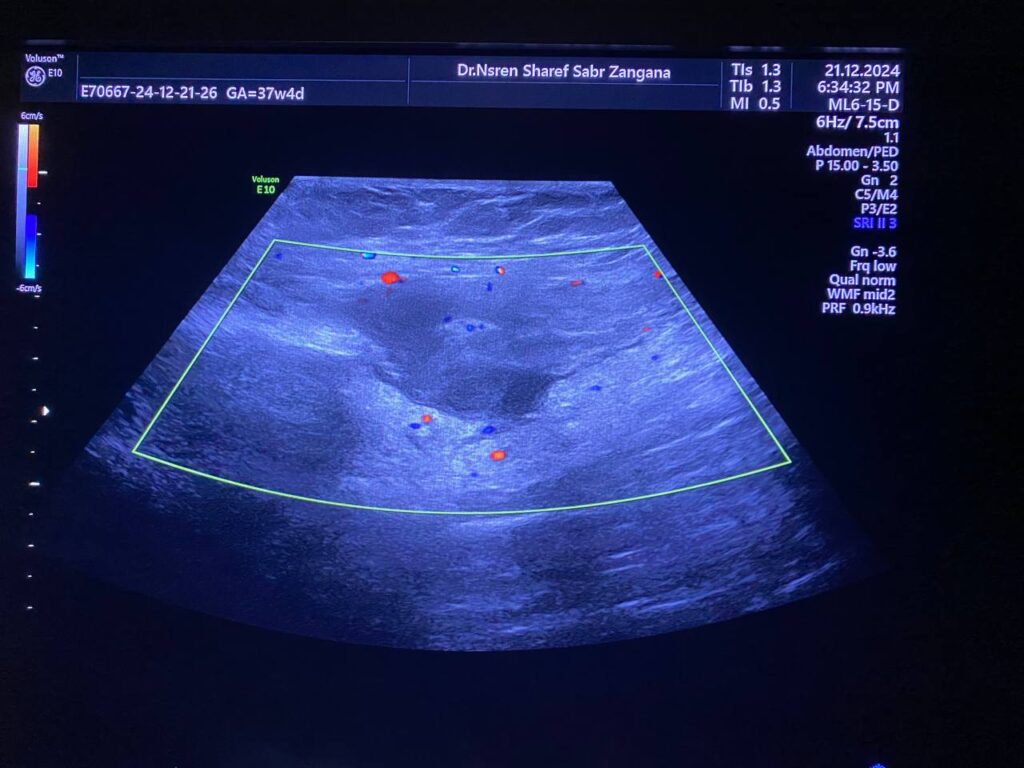

· Left ovary , normal in size , no dominate follicle , with presence of heterogenous vascular solid mass, contain calcification size about 44x30mm with indistinct margin, vascular on color doppler, score 3-4 located just the lateral to the left ovary , with invasion of the adjacent peritoneal & muscular layer ( left rectus abdominis muscle) , mostly suspicious mass , its invasion to the left ovary cannot be excluded , picture could be Desmoid tumor ? peritoneal tumor > , for further study please . no suspicious lymph node seen